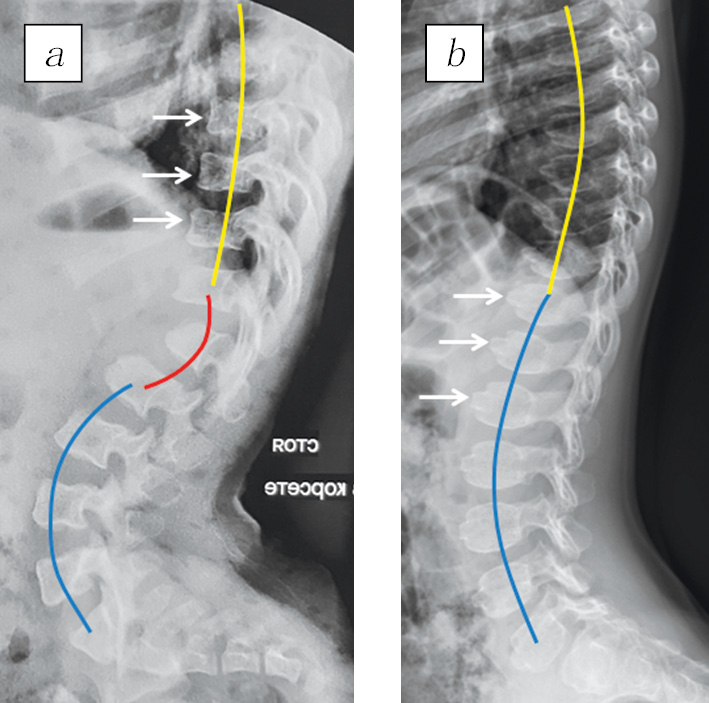

Задержка роста значительно прогрессировала с возрастом у пациентов с АХ. В возрасте до года отклонение роста от возрастной нормы колебалось от –0,51 до –5,67 (в среднем составляло –3,02 SD), а в возрасте старше года — от –2,76 до –6,66 (в среднем — –5,03 SD). В то же время показатели окружности головы у больных с АХ были выше средних: +2,59 SD (от +0,7 до +6,65). У всех пациентов с АХ отмечена задержка темпов раннего моторного развития. Большинство из них приобретали способность к самостоятельной ходьбе только к 17 мес. жизни. У 95 % детей уже на первом году жизни развивался динамический кифоз грудопоясничного перехода, который постепенно уменьшался к моменту начала самостоятельной ходьбы. Типичным клиническим проявлением была гипермобильность в межфаланговых суставах кистей, наряду с ограничением разгибания в локтевых суставах, у 74 % детей после года формировалась варусная деформация голеней, а у 100 % детей развивался поясничный гиперлордоз (рис. 3). На рентгенограммах позвоночника у детей с АХ, как правило, уже на первом году жизни выявляли грудопоясничный кифоз, сопровождающийся выраженной передней клиновидностью тел позвонков на его вершине, а также сглаженностью физиологического грудного кифоза и усилением поясничного лордоза (см. рис. 3, а). При ПСАХ доминирует аномальная оссификация апофизов тел позвонков с образованием языкообразных выступов их передних отделов, а усиление поясничного лордоза характеризуется умеренной величиной, прежде всего вследствие мышечной слабости, а не структурных изменений, как при АХ (см. рис. 3, б).

Рис. 3. Рентгенограммы грудного и поясничного отделов позвоночника в боковой проекции пациентов с ахондроплазией (а) и псевдоахондроплазией (б): а — физиологическая оссификация апофизов тел позвонков с квадратными контурами позвонков (белые стрелки); сглаженность грудного кифоза (желтая линия), патологический грудопоясничный кифоз (красная линия), усиленный поясничный лордоз (синяя линия); б — аномальная оссификация апофизов тел позвонков с языкообразными выступами передних отделов позвонков (белые стрелки); физиологическая величина грудного кифоза (желтая линия) и умеренное усиление поясничного лордоза (синяя линия)